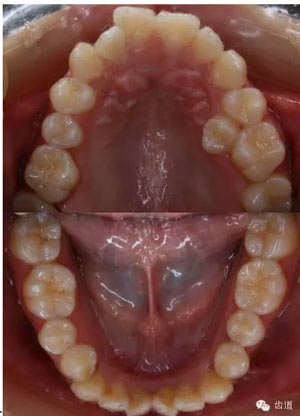

上牙弓:尖圓形,25腭側(cè)完全錯(cuò)位,26前移

下牙弓:卵圓形,下前牙區(qū)擁擠

矯治結(jié)束后口內(nèi)像

治療前后口內(nèi)相對(duì)比